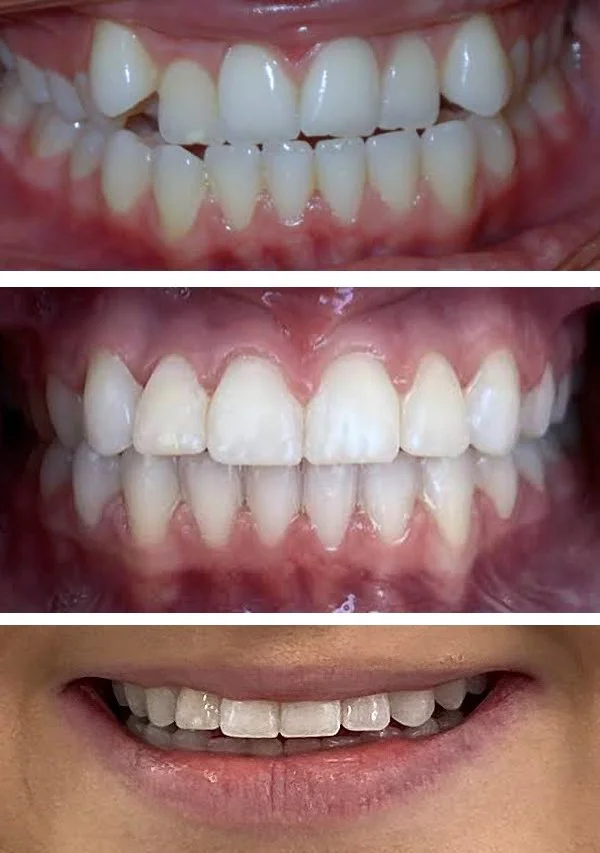

Cosmetics

We can improve the appearance of your teeth in a way tailored to you. Crowns, veneers, tooth shaping, and dental bonding may be used.

Bioclear restorations

Dental Bonding

Veneers

Tooth reshaping

Crowns

Bioclear Restorations, bonding

Restoration

Crown and Bridge